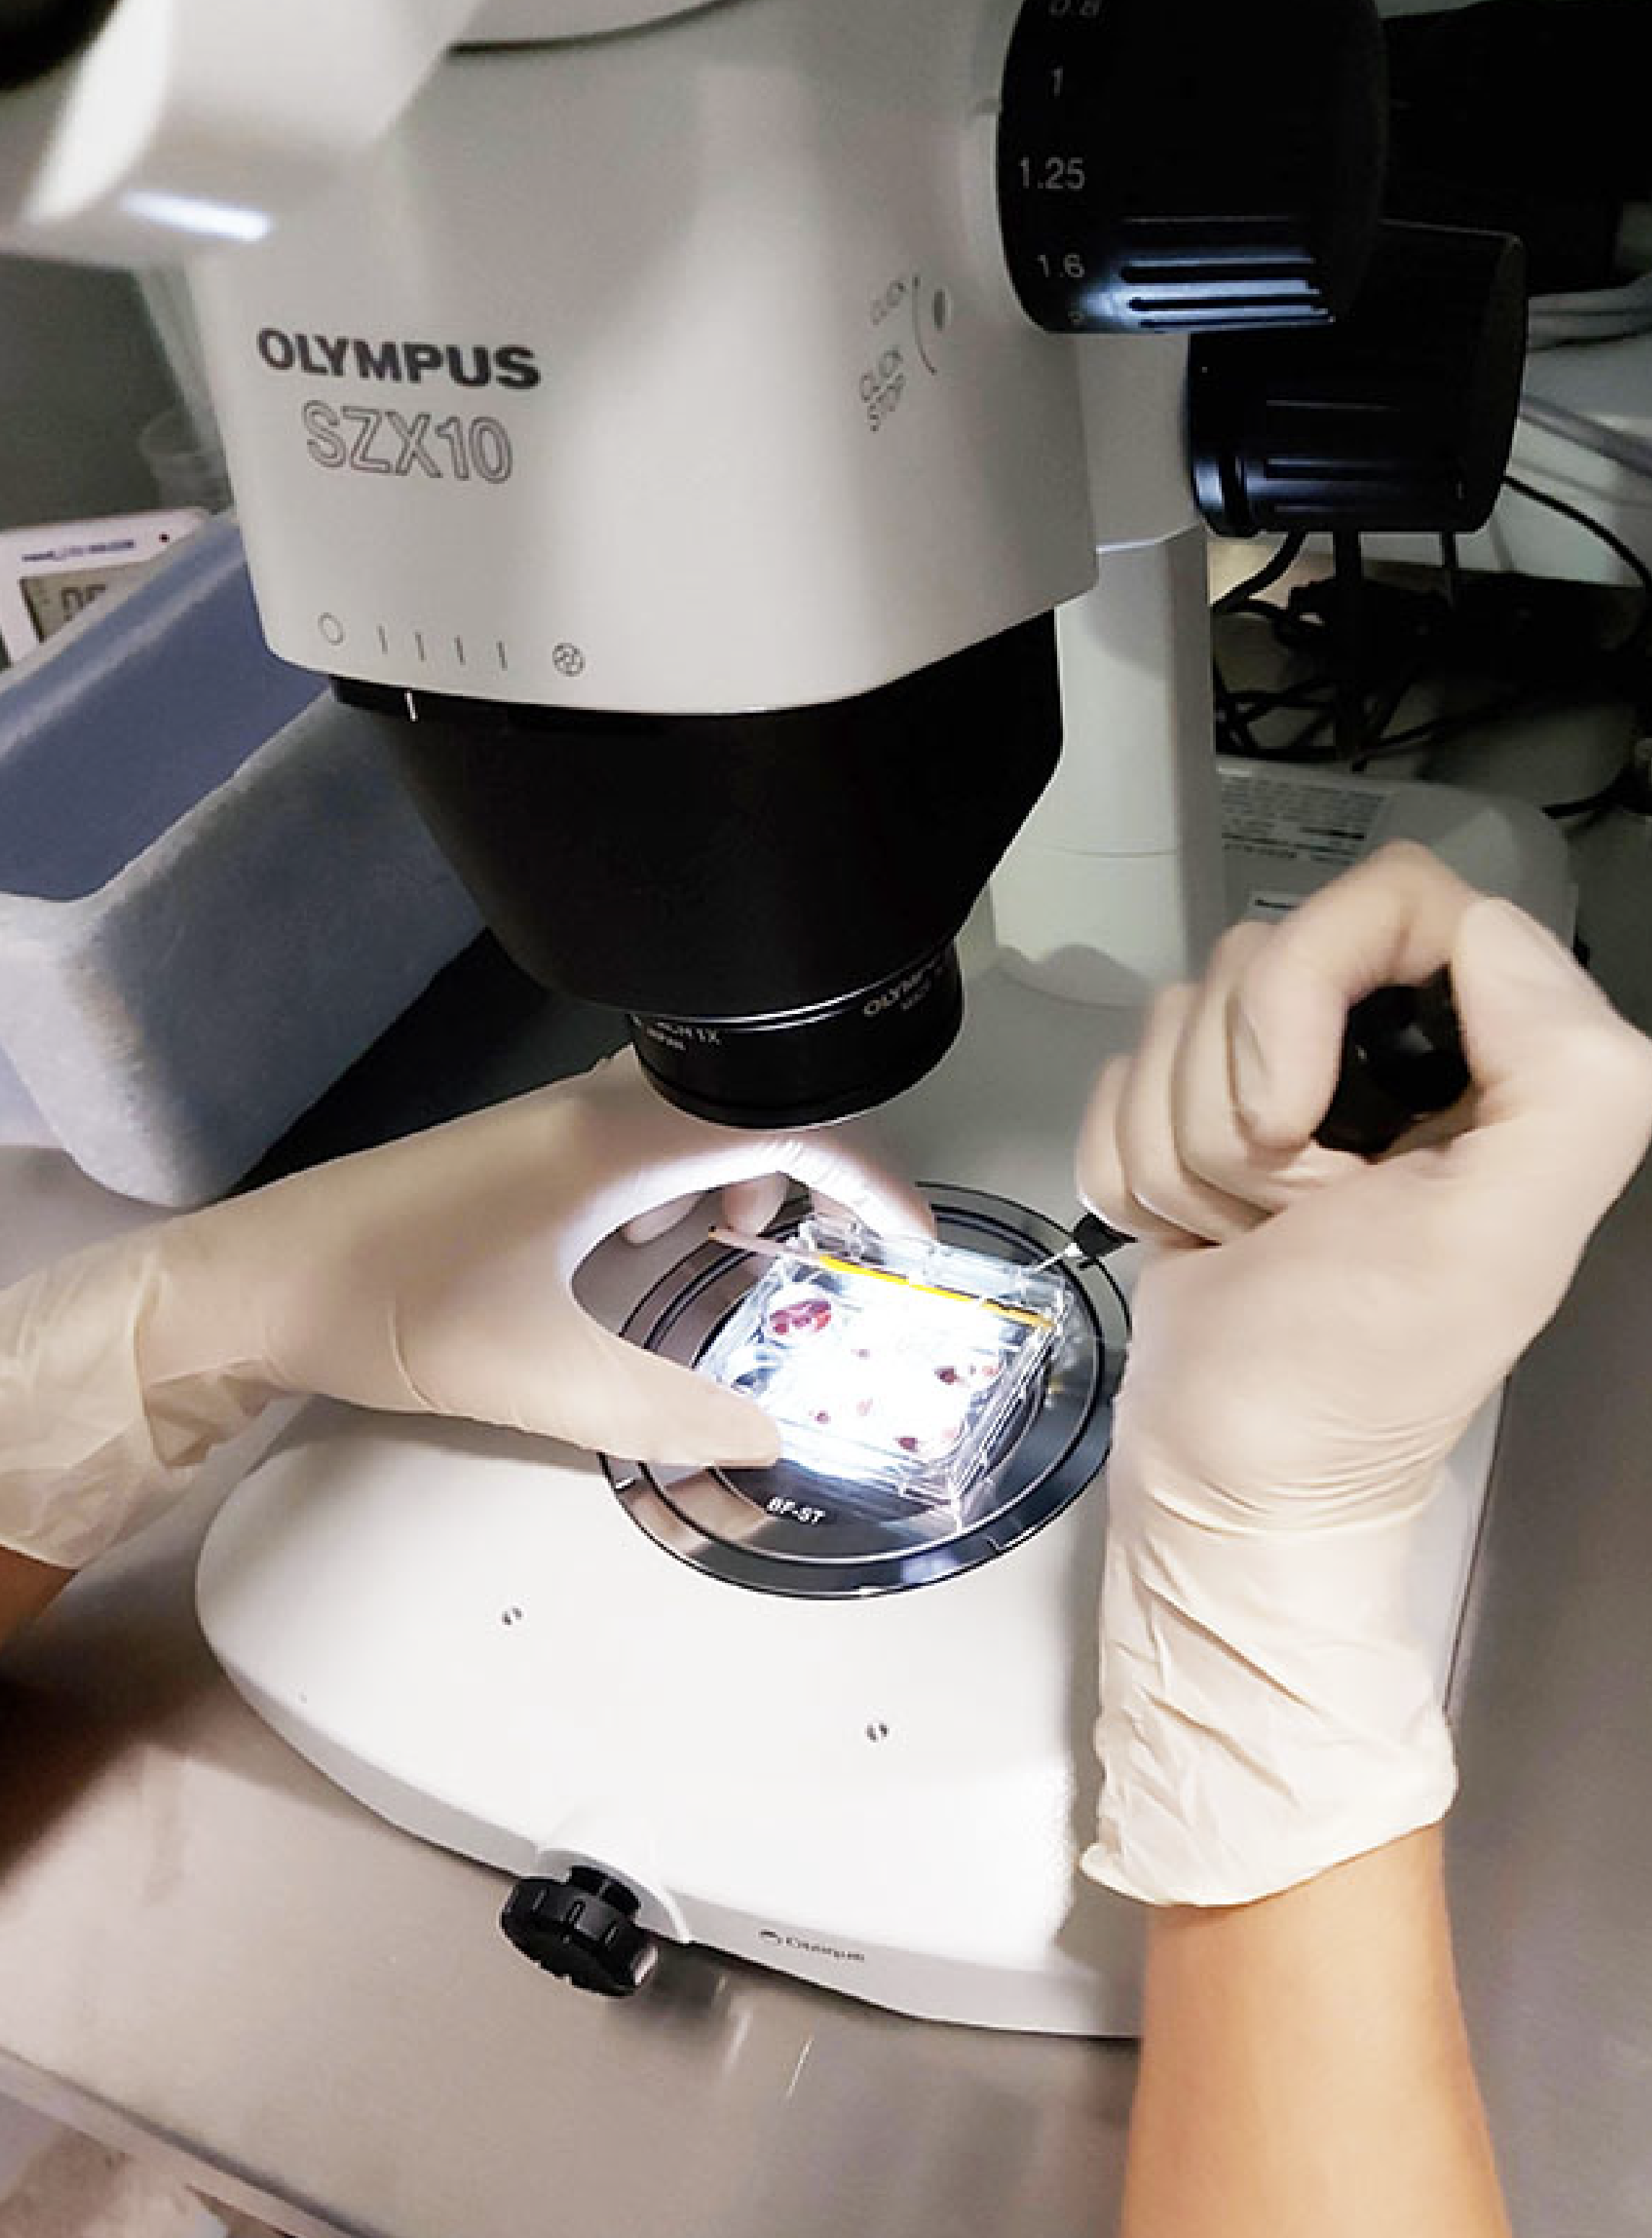

At Nydra, We help connect you with carefully selected clinical partners.

Our clinical partners are carefully selected for their experience, qualifications, and commitment to excellence. What sets us apart is our team of healthcare professionals who work in your home country—ensuring that you have the support and guidance needed to make informed decisions, and that quality is always guaranteed.

Our team includes healthcare professionals who carefully assess and coordinate each case, ensuring patients are matched with the most suitable clinical partners.

clinical partners